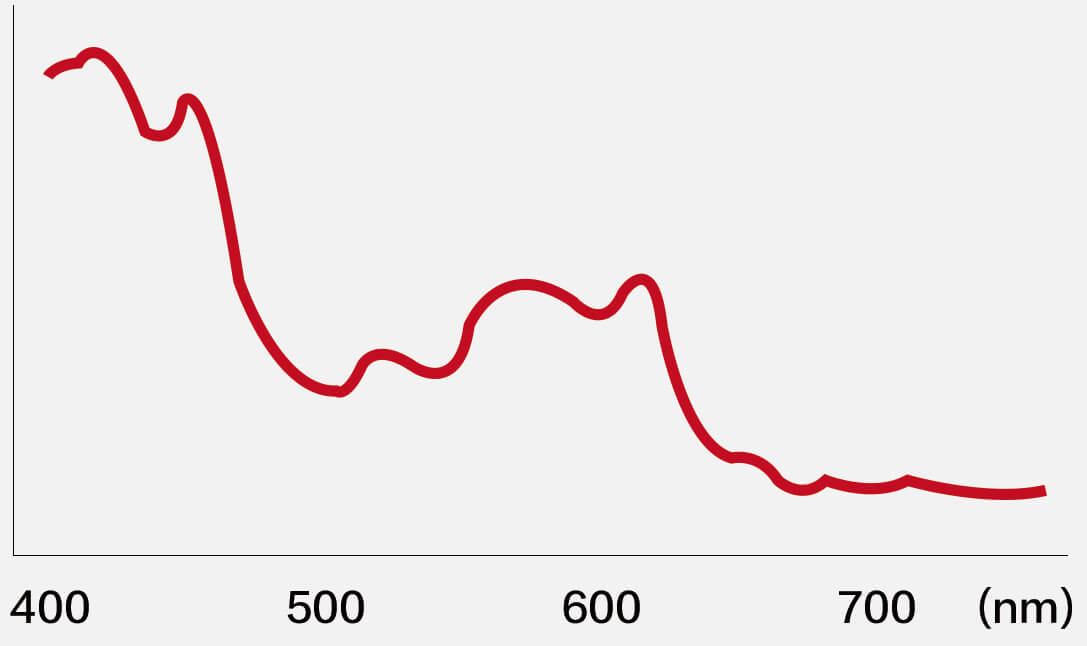

血管对比度分布光谱曲线

血管对比度分布光谱曲线

VIST光谱

VIST光谱